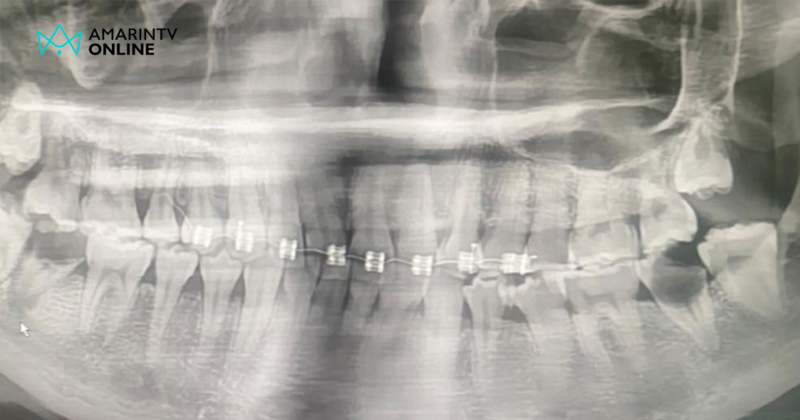

เมื่อถึงกำหนดนัด นางสาวนภัค ได้มีการทำการแนะนำการบริการจัดฟันแฟชั่น โดยมีอุปกรณ์จัดฟันแฟชั่น ทั้งลวด ยางวงที่นำไปคล้องหรือผูกติดไว้ในบริเวณช่องปากหรือบนฟัน ซึ่งเป็นสินค้าที่ห้ามขายตามคำสั่งคณะกรรมการคุ้มครองผู้บริโภค และเมื่อนางสาวนภัค เริ่มทำการจัดฟันแฟชั่นให้กับสายลับ ตำรวจจึงได้เข้ามายังสถานที่เกิดเหตุ